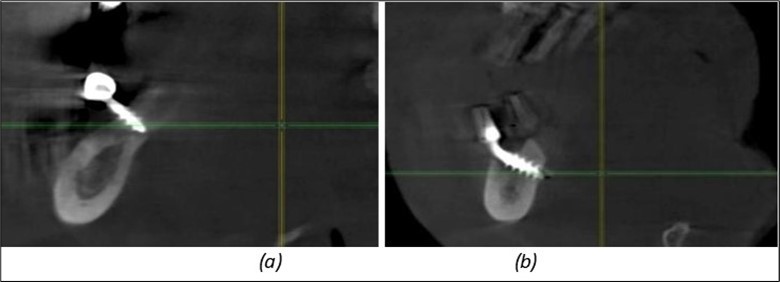

In the interforaminal area (Figure 3, Figure 13), 6 corticobasal implants are also placed. The increased number of implants is due to the poorly represented distal area that needs to be compensated.

Figure 13.Corticobasal BCS implants fixed between the vestibular and lingual cortices with support on the basal bone: (a) BCS fixed between the lateral cortices; (b) BCS implant with support on the basal cortex.

Figure 14.Rx panoramic final situation control: (a) Panoramic X-ray with the addition of a distal BCS implant in quadrant 3 at 11.2022; (b) Control X-ray, 10.2023.